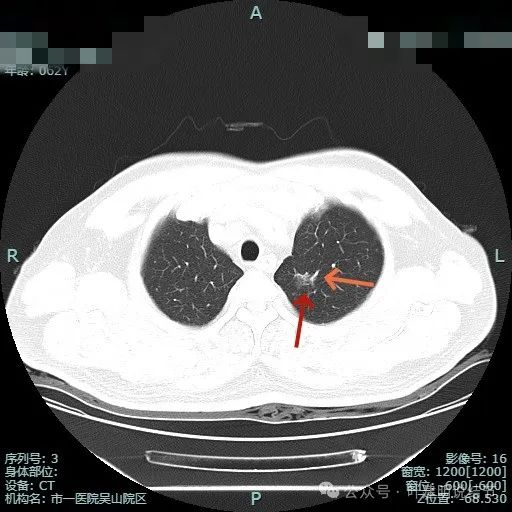

似有月牙铲征,显得像混合密度。

边缘区域表面不平。

右上叶另有病灶B:微小淡磨,轮廓较清。